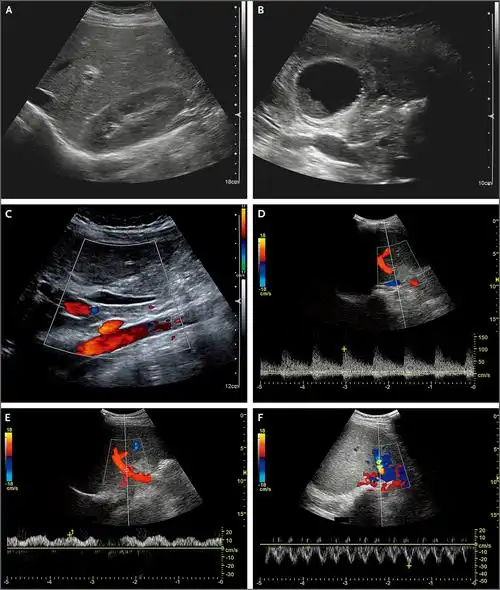

1. 腹部超声影像

腹腔干和肠系膜动脉

经典超声内镜病例之腹主动脉主要分支的探查技巧和典型病例